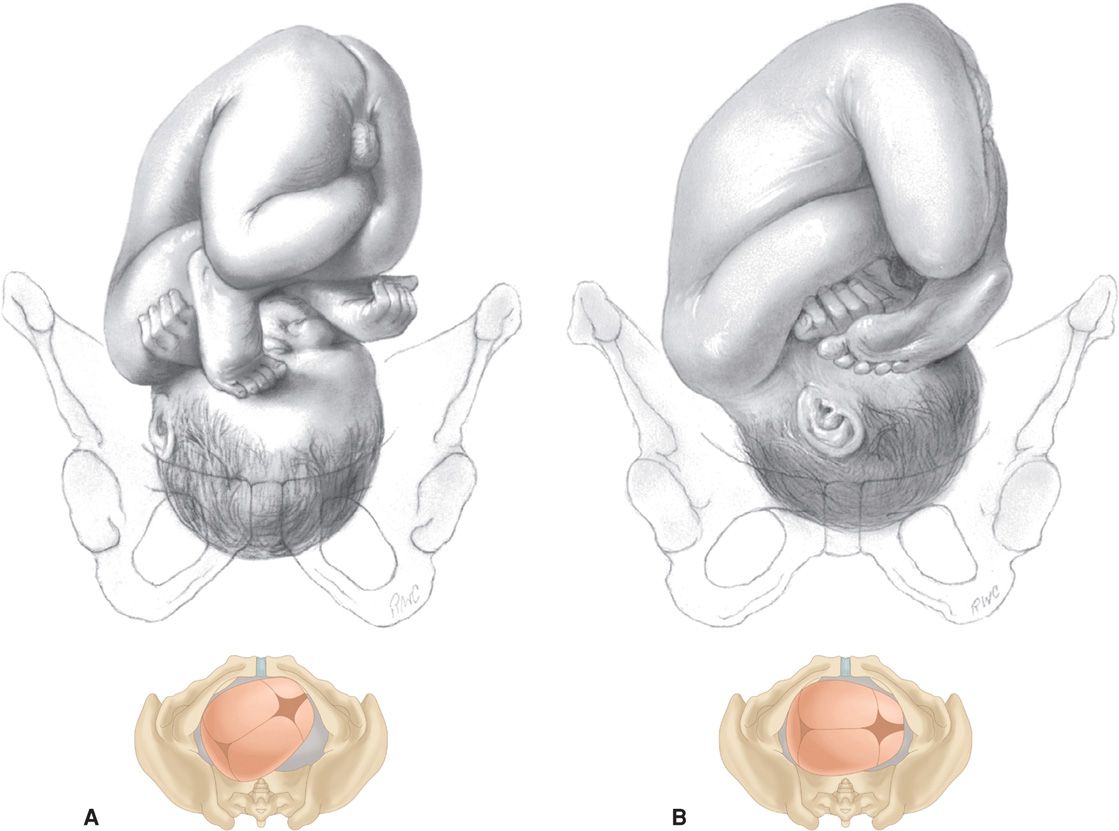

Рождение ребенка в тазовом предлежании

Первый момент биомеханизма родов при тазовом предлежании